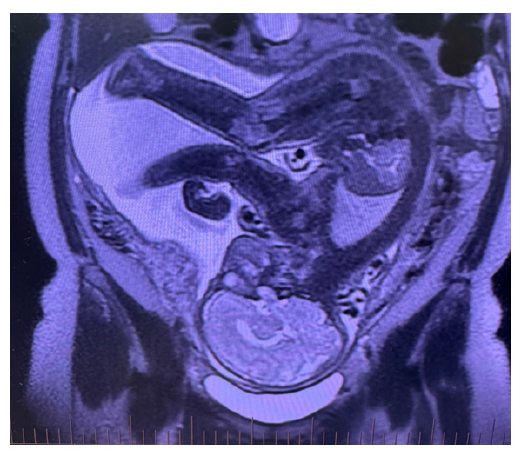

On the second-trimester anatomic ultrasound, suspected partial agenesis of the corpus callosum was raised, prompting fetal MRI at 28 weeks’ gestation. MRI found no fetal abnormality and revealed an arcuate uterus. Fetal biometry was appropriate for gestational age (~22nd percentile) (Figure 1).

Figure 1:A coronal T2-weighted Foetal MRI sequence of the pelvis showing an arcuate uterus.